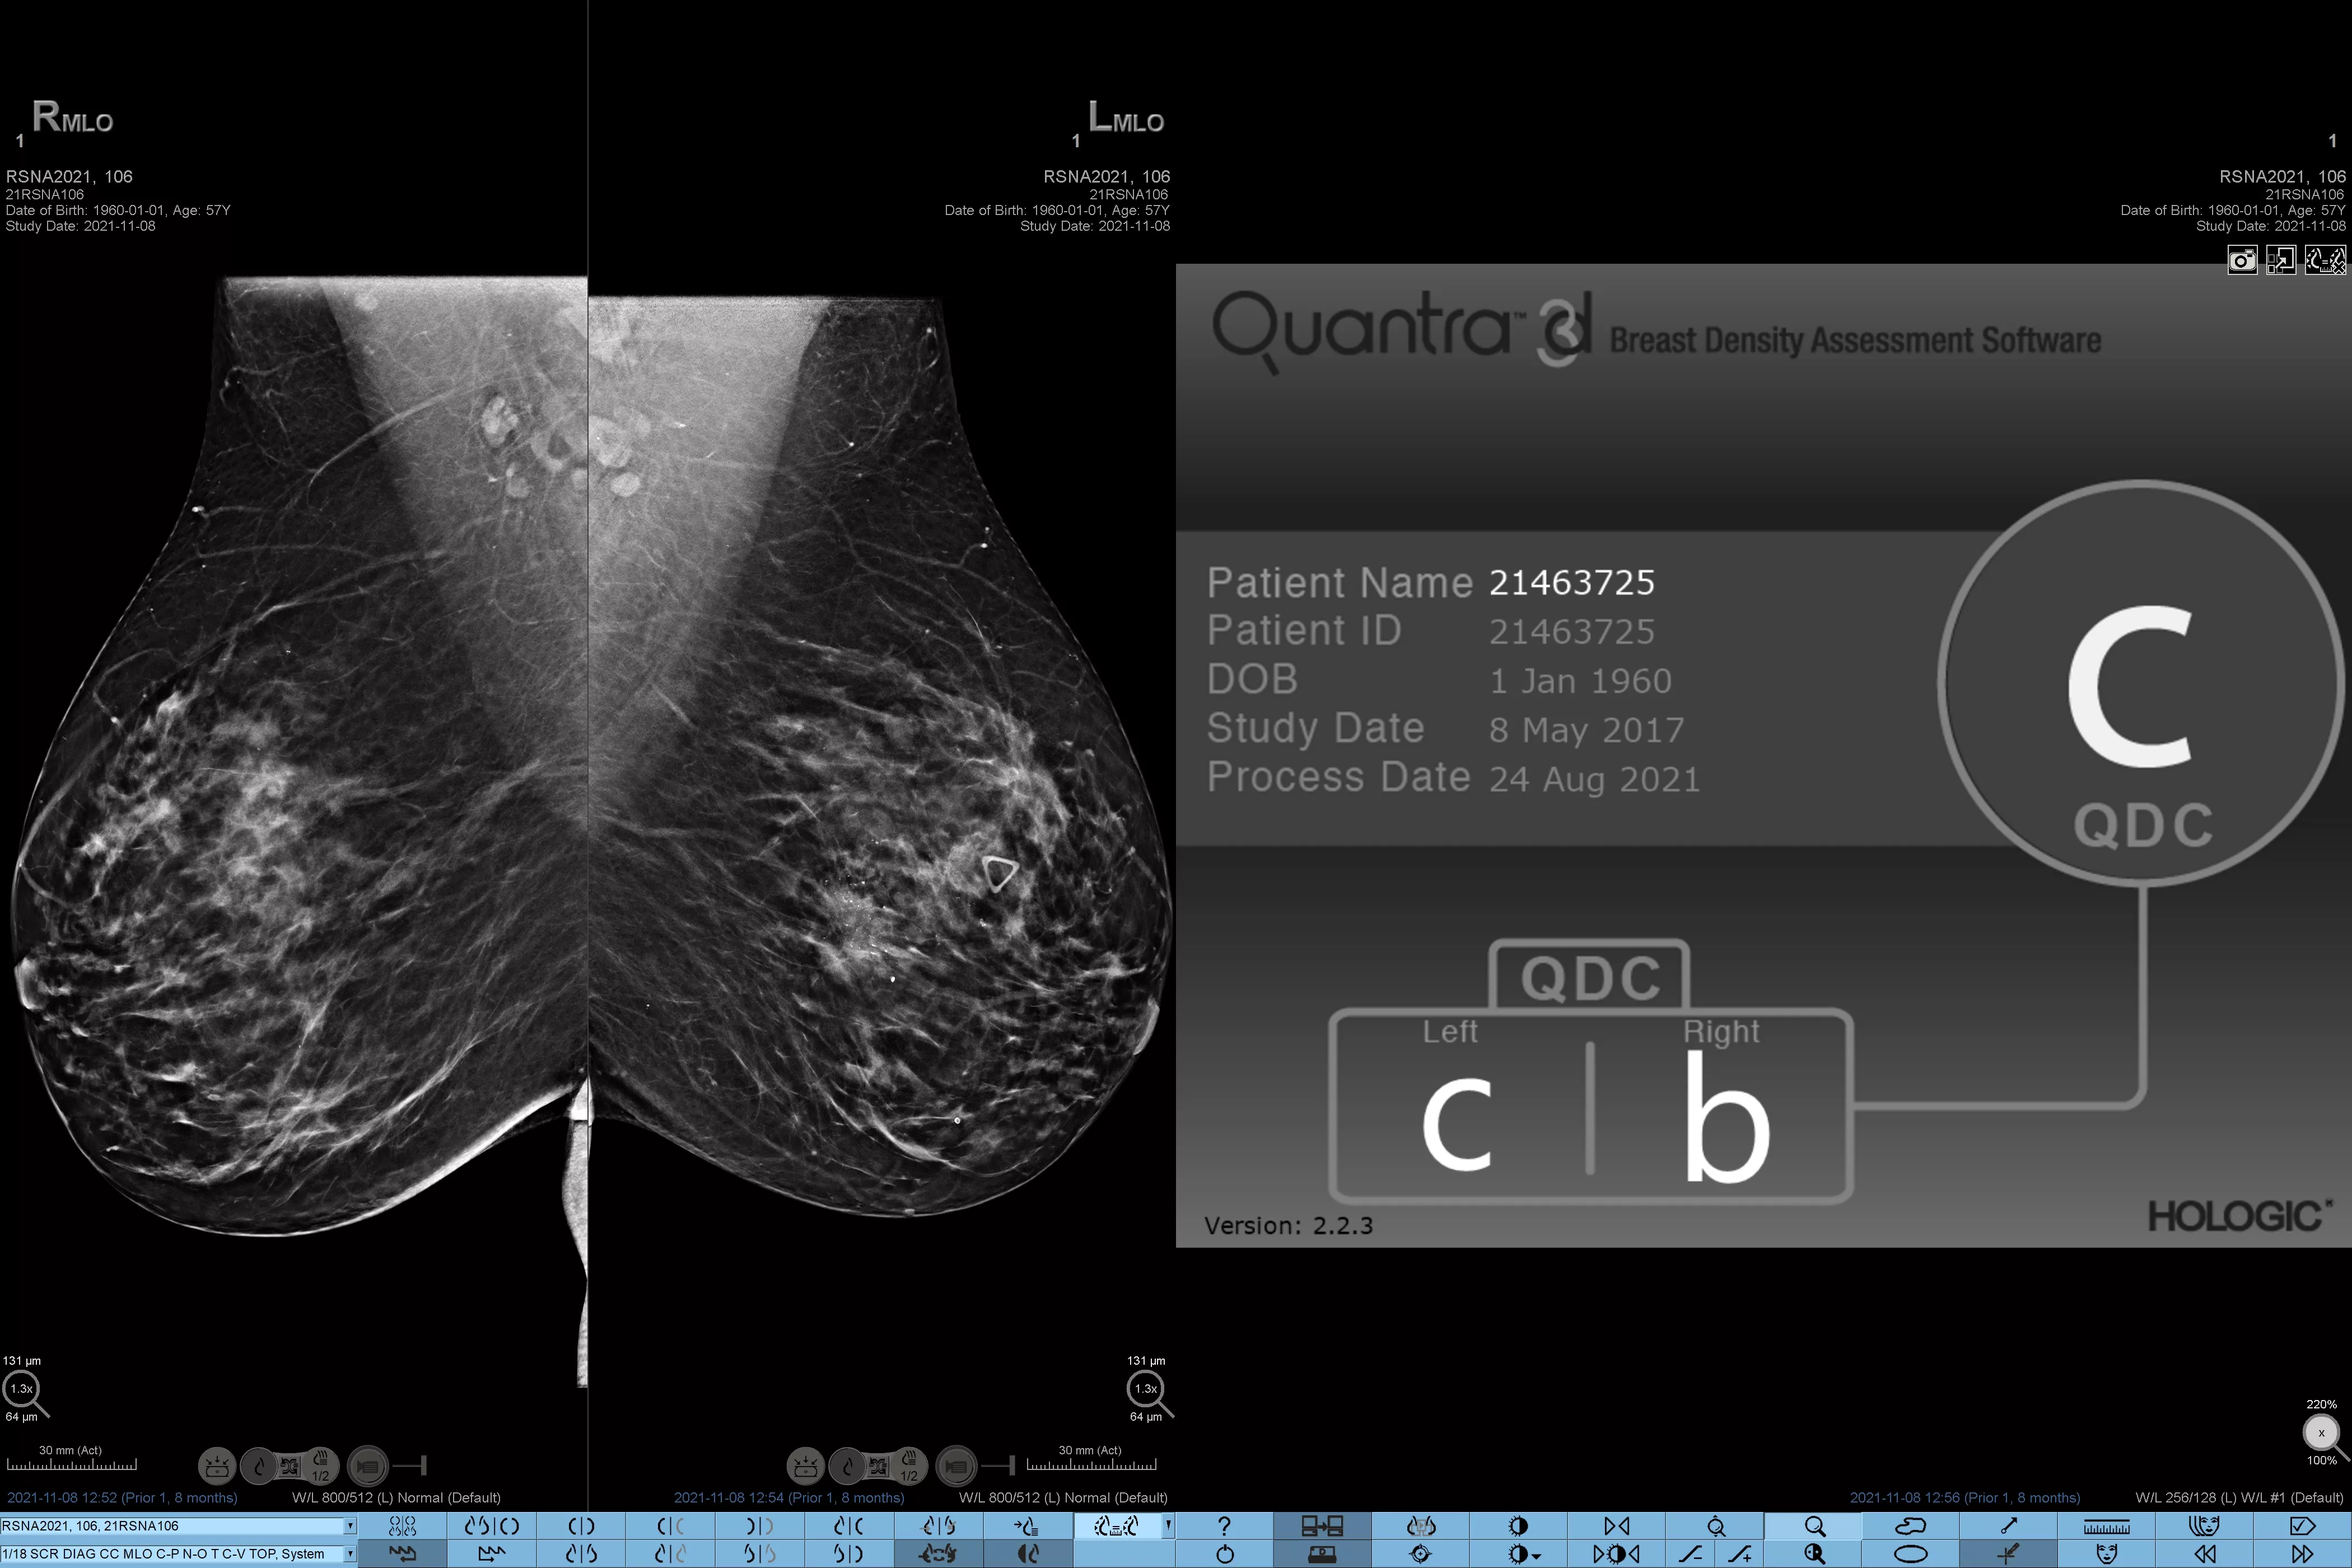

Sabemos que una densidad mamaria alta aumenta el riesgo de cáncer de mama en mujeres.1 Por tanto, es fundamental realizar un análisis preciso y sin sesgo. El software de la tecnología Quantra, basado en aprendizaje automático, analiza las imágenes 2D™ y de tomosíntesis para determinar la distribución y la textura del tejido parenquimatoso. Clasifica las mamas en cuatro categorías de composición mamaria de acuerdo con las directrices del Atlas BI-RADS (5.ª edición) del American College of Radiology (ACR).2

Además del volumen, el patrón y la textura del tejido fibroglandular pueden ser igualmente decisivos para la predicción mamográfica del riesgo de cáncer.3-5 ​​Mediante el análisis y la clasificación de la textura y el patrón de la mama, nuestra tecnología puede ofrecer la información precisa que necesita para realizar una clasificación más fiable y completa y, de este modo, diseñar con seguridad una vía de detección específica para cada paciente.

El algoritmo de aprendizaje automático objetivo asigna una categoría de densidad de mama de acuerdo con los patrones y la textura del tejido de la mama.

* Las clasificaciones se basan en las categorías BI-RADS del ACR, de acuerdo con las directrices revisadas publicadas en el Atlas BI-RADS (5.ª edición) del American College of Radiation (ACR). Estas directrices tienen en cuenta el patrón y la textura, y no solo el volumen, a la hora de determinar la densidad.